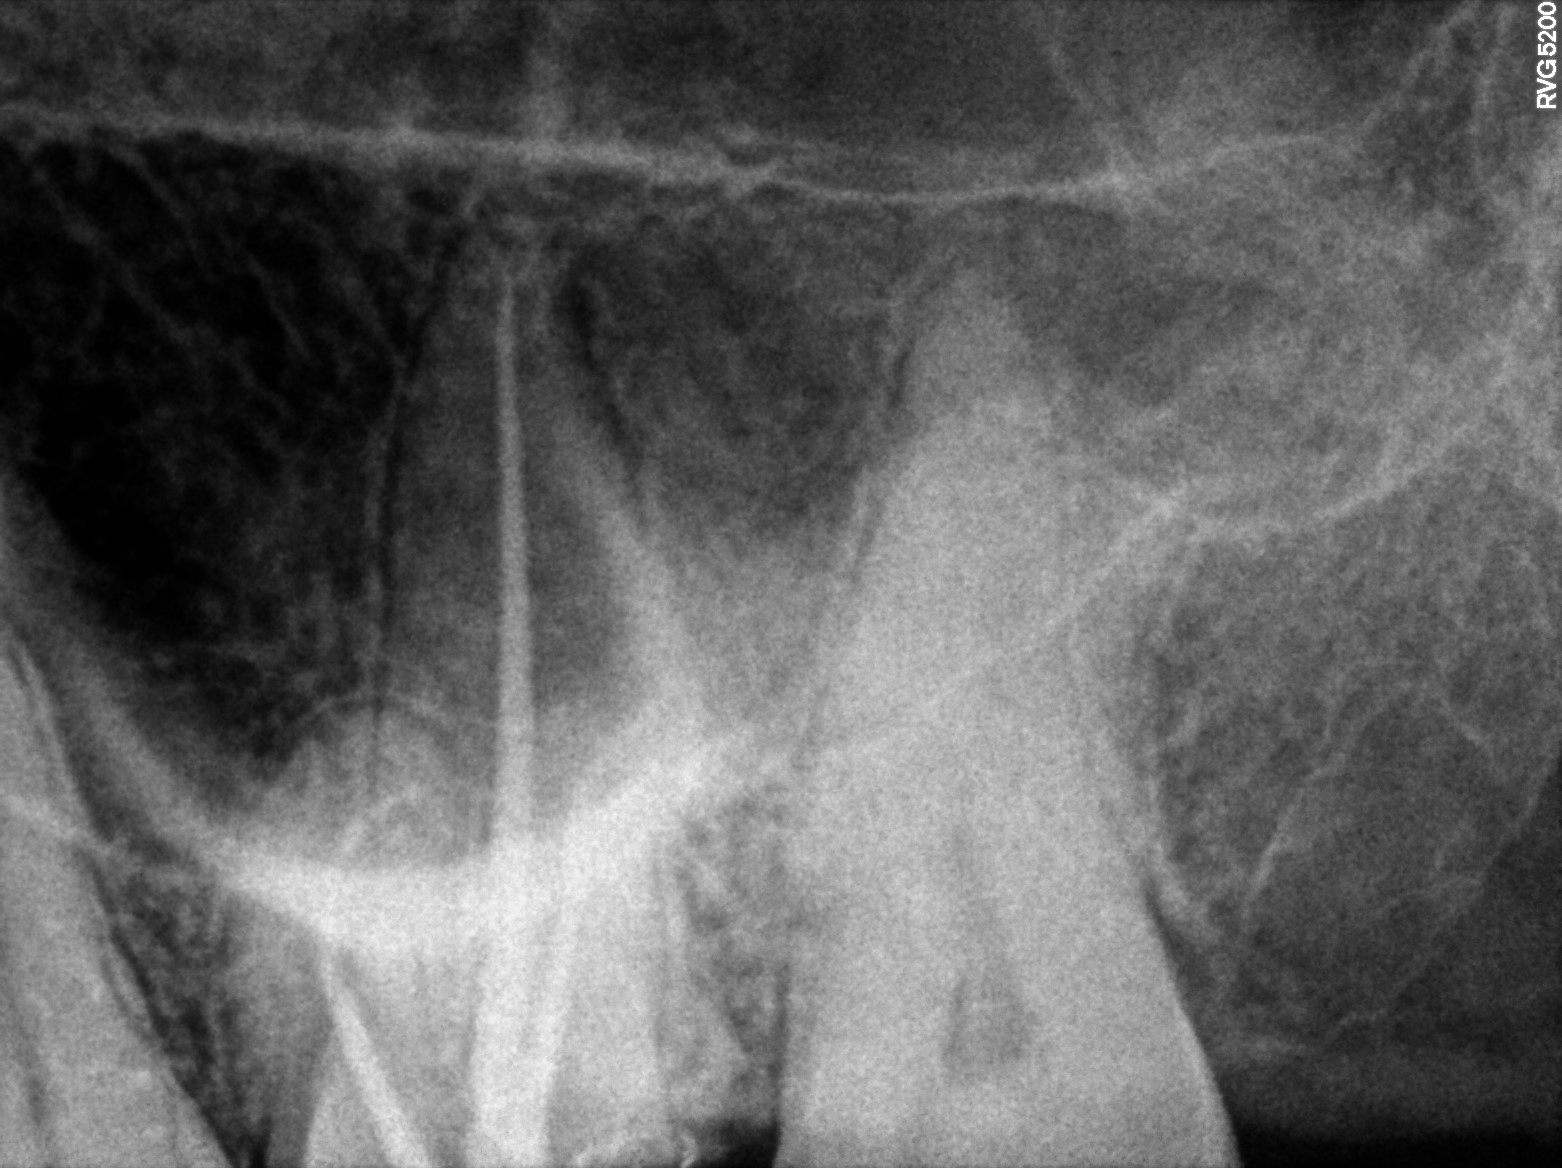

Dental Radiographs FHIR: DocumentReference · LOINC 24641-7

xray_1747409705_0.jpg

24641-7